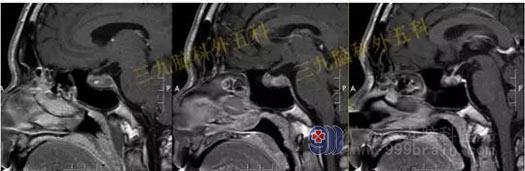

头部MR检查提示:鞍区短T1稍短T2异常信号影,大小约8mm×10mm×10mm,垂体受压下移,垂体柄受压后移。视交叉轻度受压上抬。鞍区异常信号影,考虑Rathke's囊肿可能性大。

手术过程:完善相关检查后行内镜经鼻蝶鞍区Rathke’s囊肿切除术,通过微创全切囊肿。

术后MR检查提示:经鼻蝶鞍区占位性病变切除术后改变,原病变已切除。